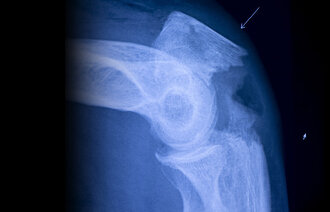

Hoftebrudd er en alvorlig og vanlig fallskade, som nesten bare rammer eldre, og særlig utsatt er de som er skrøpelige eller har beinskjørhet. Om lag halvparten av hjemmeboende eldre som får et hoftebrudd, kommer aldri tilbake til det funksjonsnivået de hadde før skaden med tanke på gangfunksjon og å være selvhjulpen hjemme (3, 4). Ifølge det nasjonale hoftebruddregisteret dør 24 prosent av pasientene med hoftebrudd i løpet av det første året etter skaden. Norge har også en av verdens høyeste forekomster av hoftebrudd med cirka 9000 brudd årlig.

Beinskjørhet (osteoporose) er en viktig årsak til at eldre som faller, skader seg oftere, og at disse skadene blir så alvorlige. Typiske lavenergibrudd, det vil si fall fra stående høyde eller lavere, er hoftebrudd, kompresjonsbrudd i ryggen samt brudd i håndledd eller overarm. Særlig utsatte er de som har hatt tidligere brudd eller har falt flere ganger. Andre risikofaktorer er å ha beinskjørhet i familien, bruk av kortison, å være underernært, røyking eller rusmisbruk.